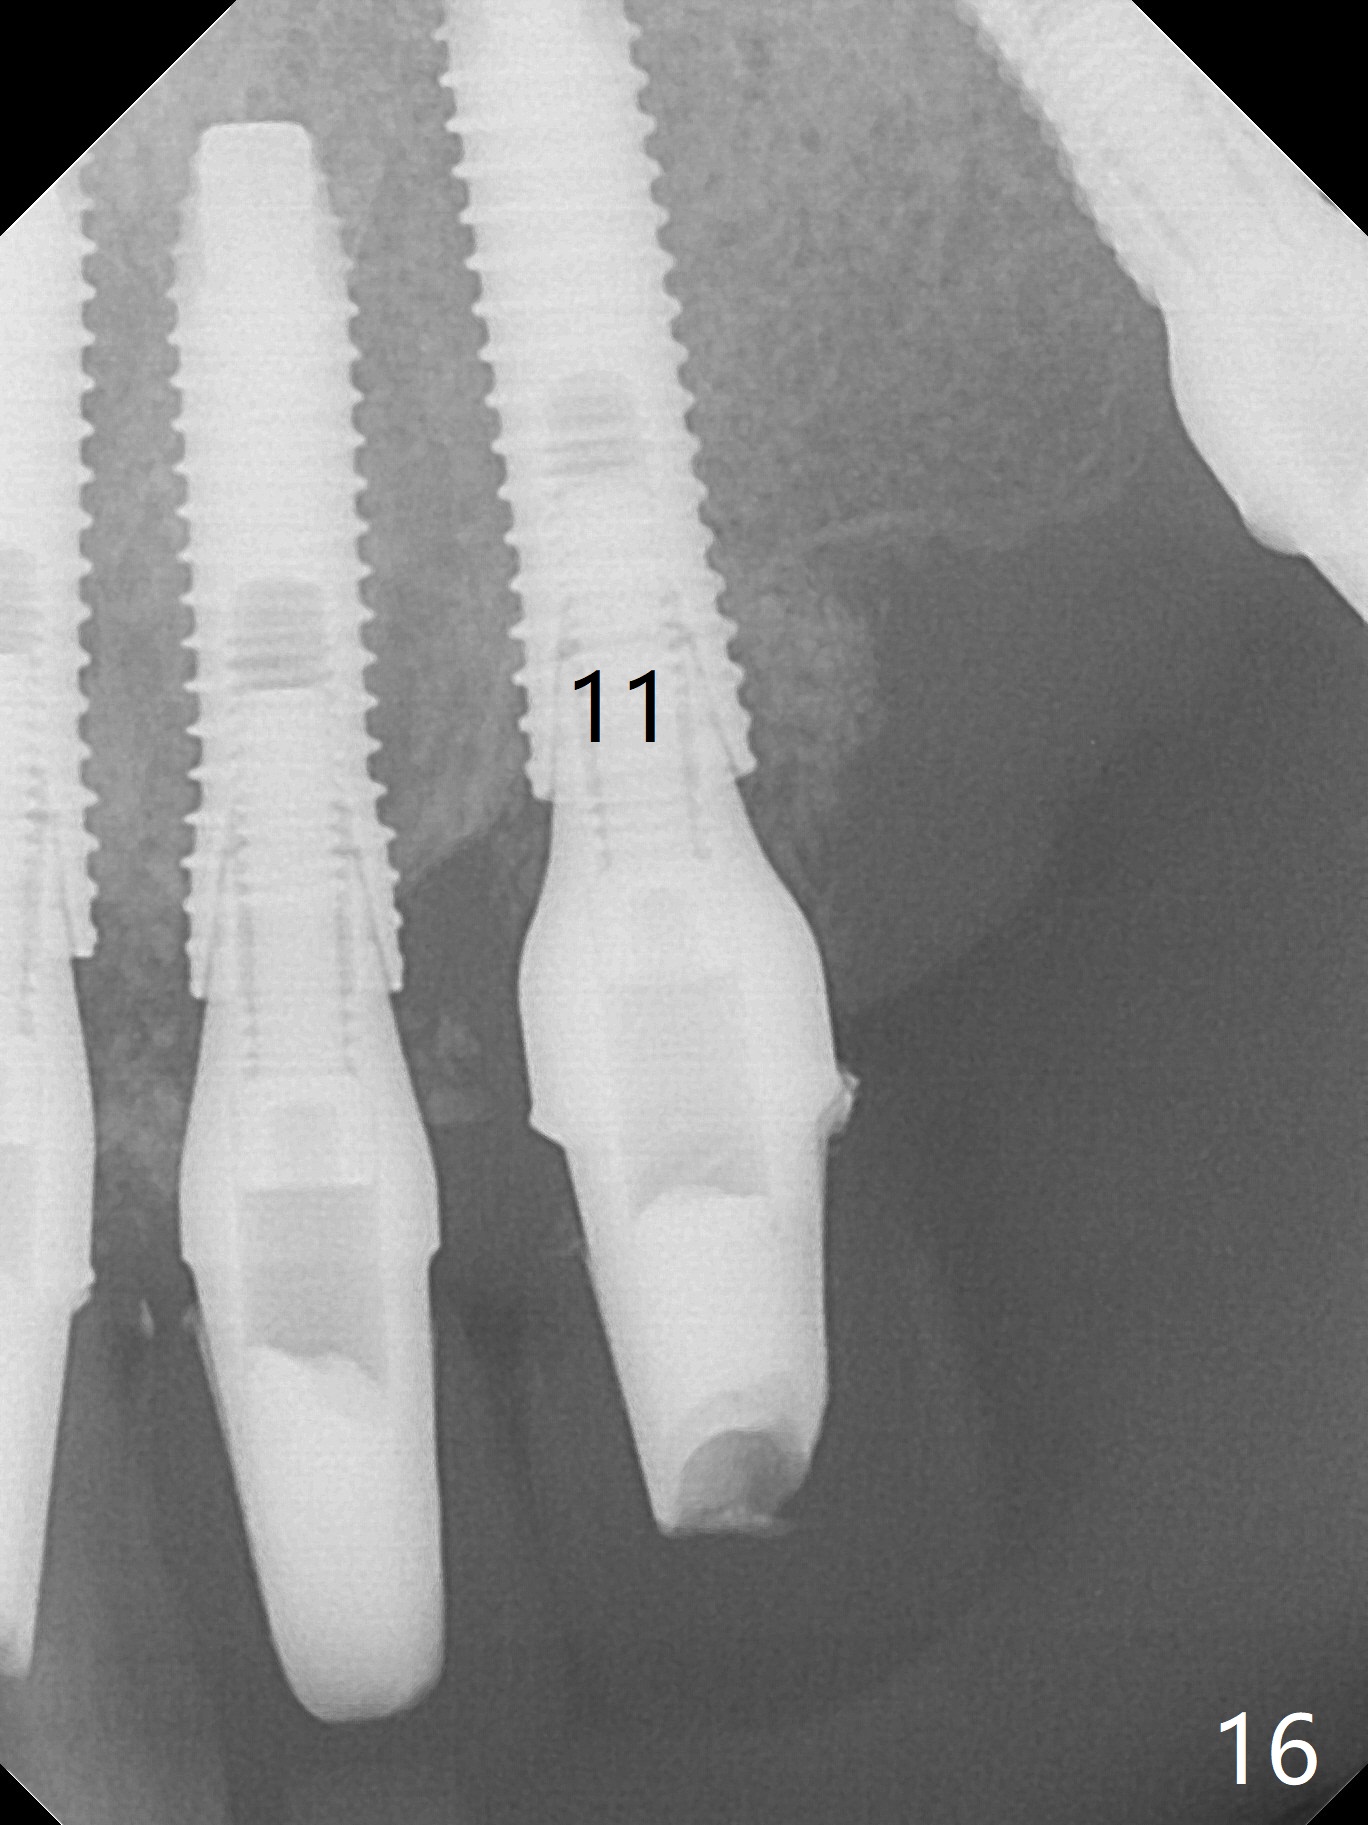

After use of 3 mm drill, the implant is reinserted at #11 with ideal trajectory (Fig.7). After further seating of the implant at #11, graft is placed in the remaining sockets of #9-11 (Fig.8 *; later more graft is placed mesial to #11 implant (^)). There appears no thread exposure 7 months postop (Fig.15,16).